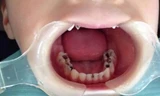

![]() |

| Khối tóc sau khi được bác sĩ lấy từ dạ dày bệnh nhi đã kết chặt với nhau |

Quá trình nội soi, ê kíp ghi nhận, dạ dày bệnh nhi phình to. Sau khi xẻ dạ dày các bác sĩ ghi nhận, búi tóc đã kết lại thành một khối rất chặt. Toàn bộ búi tóc đã được lấy ra ngoài thành công. Sau phẫu thuật, sức khỏe bệnh nhân hồi phục nhanh chóng, đi lại, sinh hoạt bình thường.